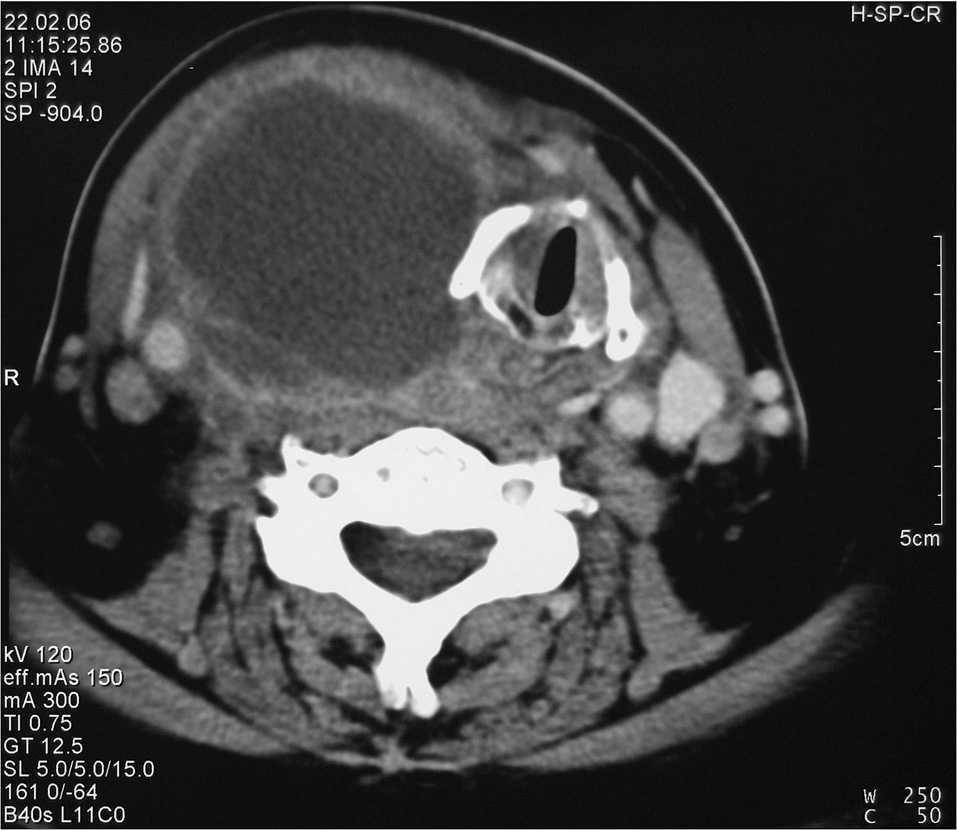

Fig. 1. Tomografía computarizada cervical. Absceso tiroideo derecho. Caso 2.

La infección bacteriana del tiroides es un proceso excepcional debido a que la glándula es muy resistente a la invasión microbiana por su elevado aporte sanguíneo, amplia red linfática, alto contenido en yodo y completo encapsulamiento1, lo que siempre deben indicar la existencia de anomalías anatómicas. Se han descrito tiroiditis supuradas en relación con quistes branquiales, persistencia del conducto tirogloso y, sobre todo, con fístulas de los senos piriformes. Los senos piriformes son estructuras procedentes de la tercera o cuarta bolsa faríngea2. Hemos tenido ocasión de tratar 2 casos: uno tras punción-biopsia-aspiración, y otro espontáneo (fig. 1), ambos producidos por Staphylococcus aureus resistente a la meticilina.